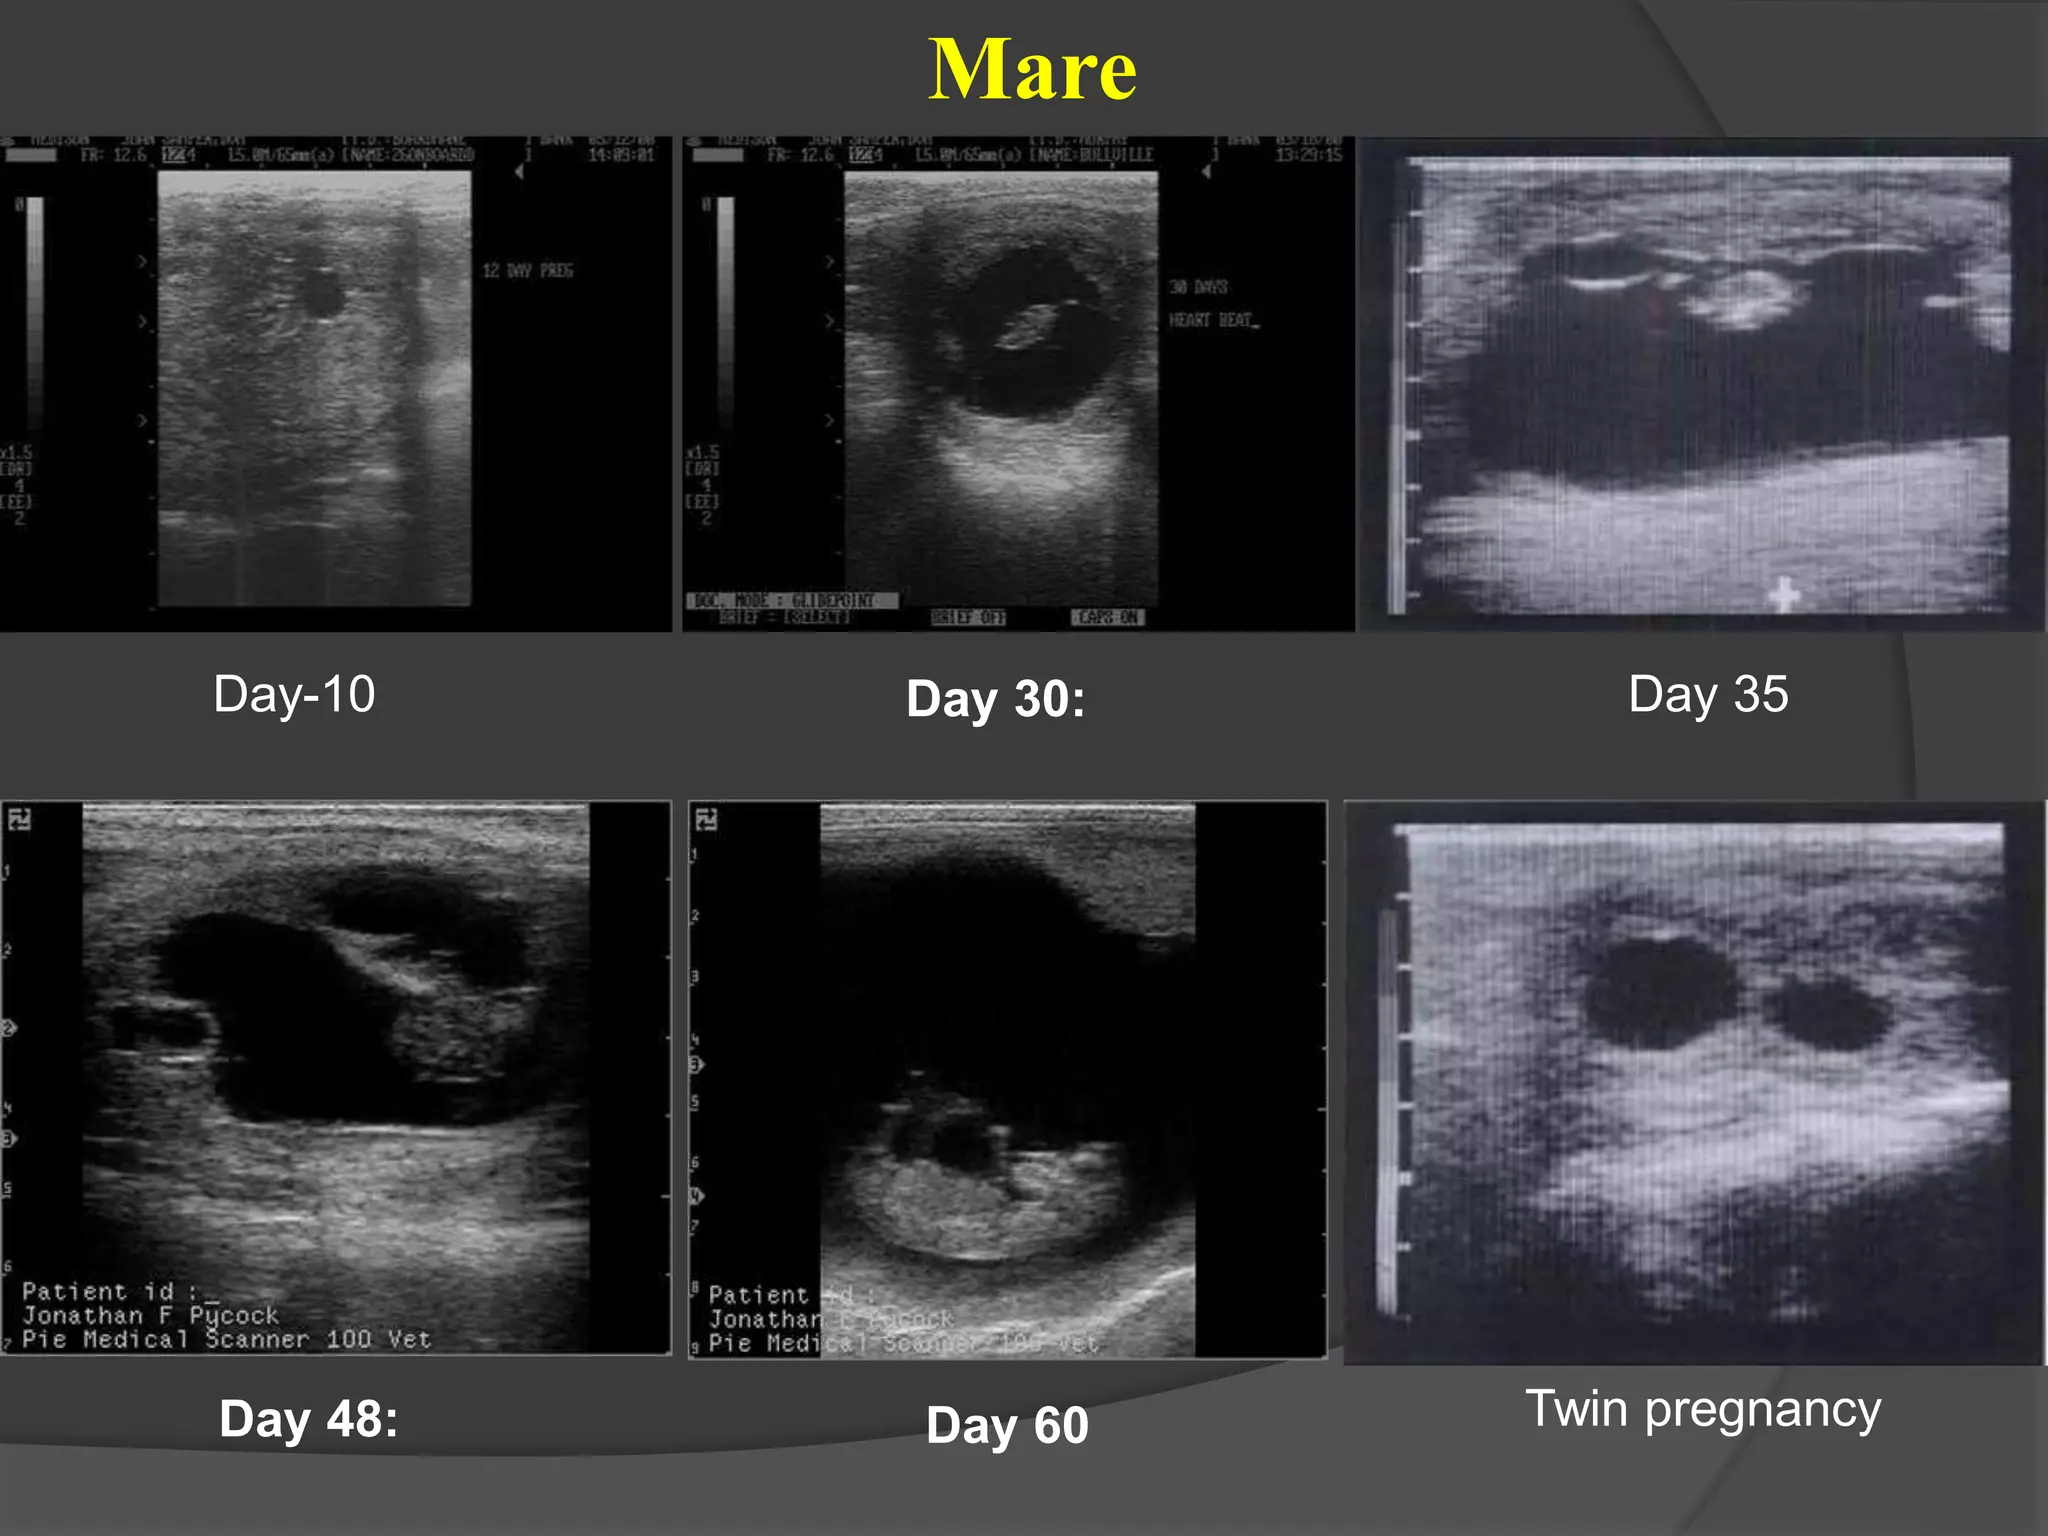

Day-10 Day 30:

Day 48: Day 60

Day 35

Twin pregnancy

Mare

Day-10 Day 30: Day48: Day 60 Day 35 Twin pregnancy Mare